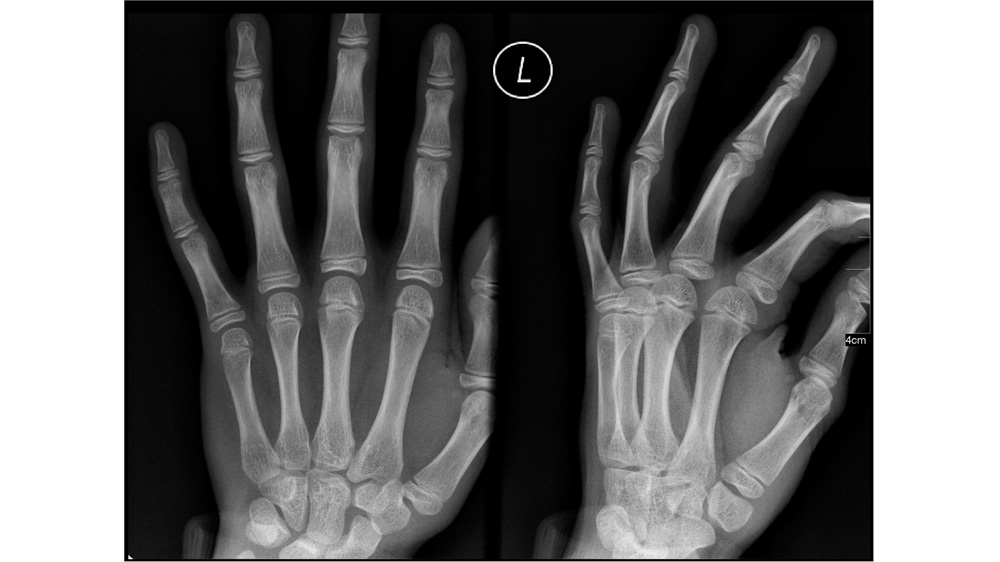

L'imagerie médicale est de loin la source d'informations la plus importante et possédant la croissance la plus rapide dans l'industrie de la santé. Les chercheurs d'IBM estiment qu'elle représente au moins 90% du total des données médicales d'aujourd'hui, mais ce qui engendre également des défis qui doivent être relevés. Le volume des images médicales peut être massif même pour les plus grands spécialistes et les radiologues de certains hôpitaux se retrouvent soumis à des milliers d'images chaque jour.